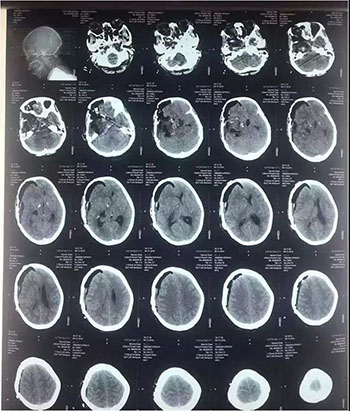

颅眶沟通性肿瘤切除手术

术前

术后(肿瘤全切)